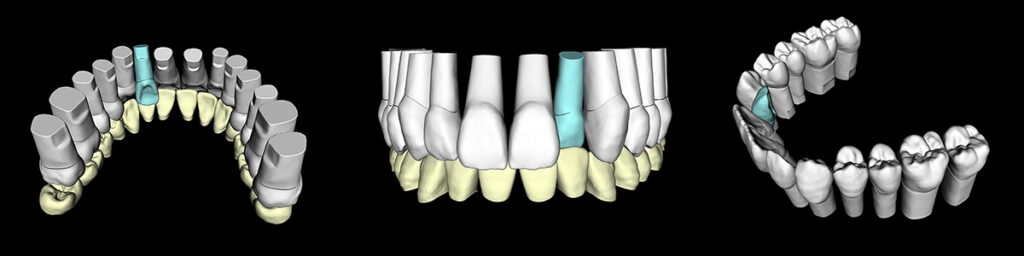

模型により術前記録と全体像を把握